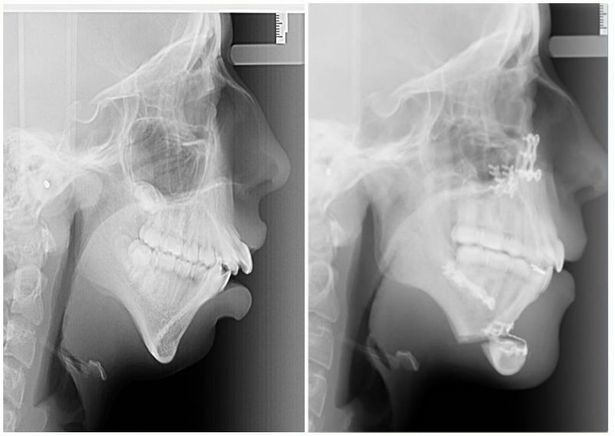

В 16 лет Элли перенесла первую операцию. Разницу можно увидеть на рентгеновском снимке: челюсти «подкроили» по вертикали и по горизонтали, а также нарастили подбородок до нормальных размеров